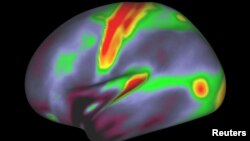

A map of myelin content (red, yellow are high myelin; indigo and blue are low myelin) in the left hemisphere of cerebral cortex is pictured in this undated handout image.

The regions were mapped based on features such as cortical thickness and the amount of insulation, called myelin, around nerve-cell connections.